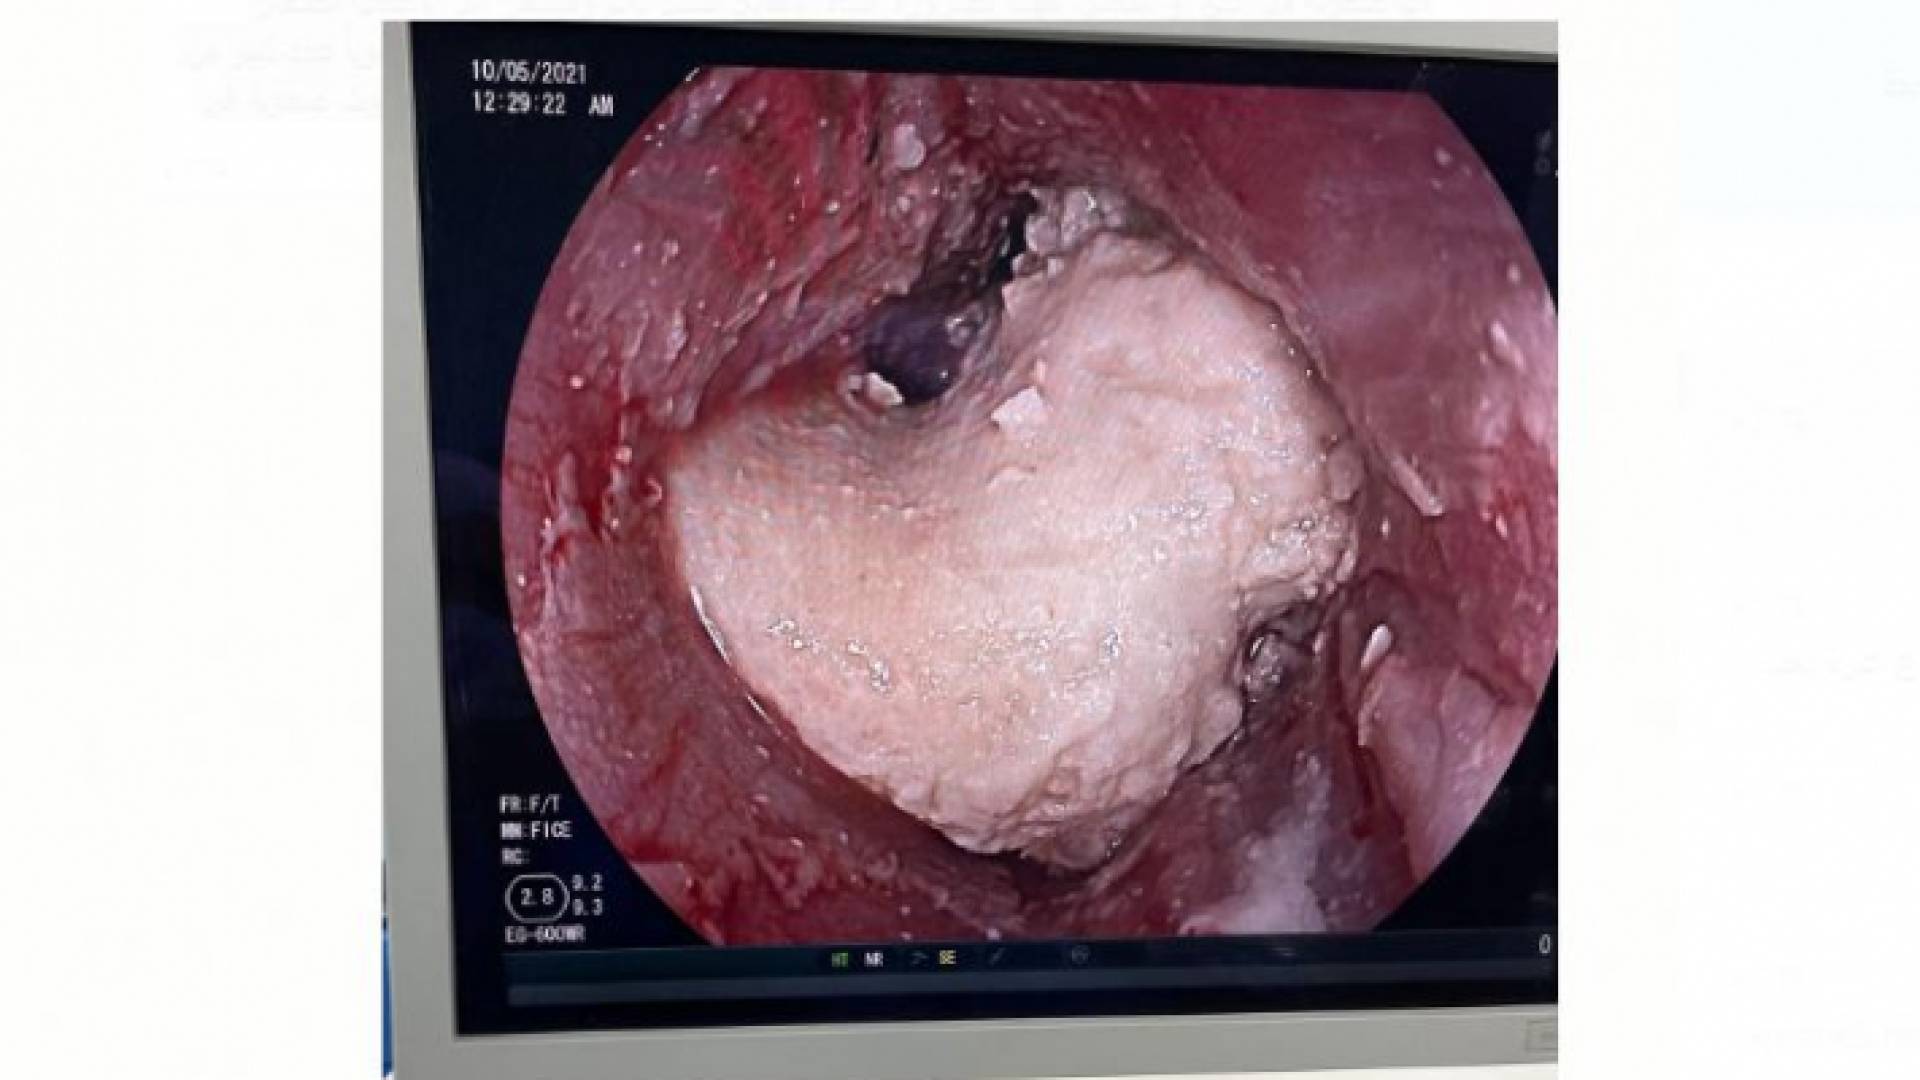

صورة من العملية

وبين الدكتور خضير أن التنظير قد أظهر وجود قطعة الجميد في المريء مغلقة إياه تماما، وتم محاولة إزالتها باستخدام الملقط الخاص بإزالة الأجسام الصلبة (Rat tooth forceps) و (Polypectomy snare) بالإضافة إلى استخدام الماء الدافىء لتذويبها.

وبعد مرور ما يزيد على ساعتين تمكن الفريق من عمل فتحة صغيرة في طرف قطعة الجميد وإدخال بالون صغير من خلالها يستخدم عادة في توسعة القنوات الصفراوية (ERCP balloon)، حيث تم إدخال البالون من خلال قطعة الجميد إلى أسفل منها، وبعد نفخ البالون وتحريكه بدأت قطعه الجميد بالتكسر تدريجيا، واستمر العمل بعد ذلك لتفتيت القطعة الصلبة إلى أجزاء صغيرة، وإزالة جزء من قطعة الجميد خارج المريء ودفع الجزء المتبقي من القطعه إلى المعدة.